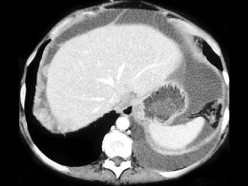

55岁,女性,结合图像,最可能的诊断是()

• A.卵巢癌扩散

• B.结核性腹膜炎

• C.胃癌

• D.腹膜炎

• E.以上都不是